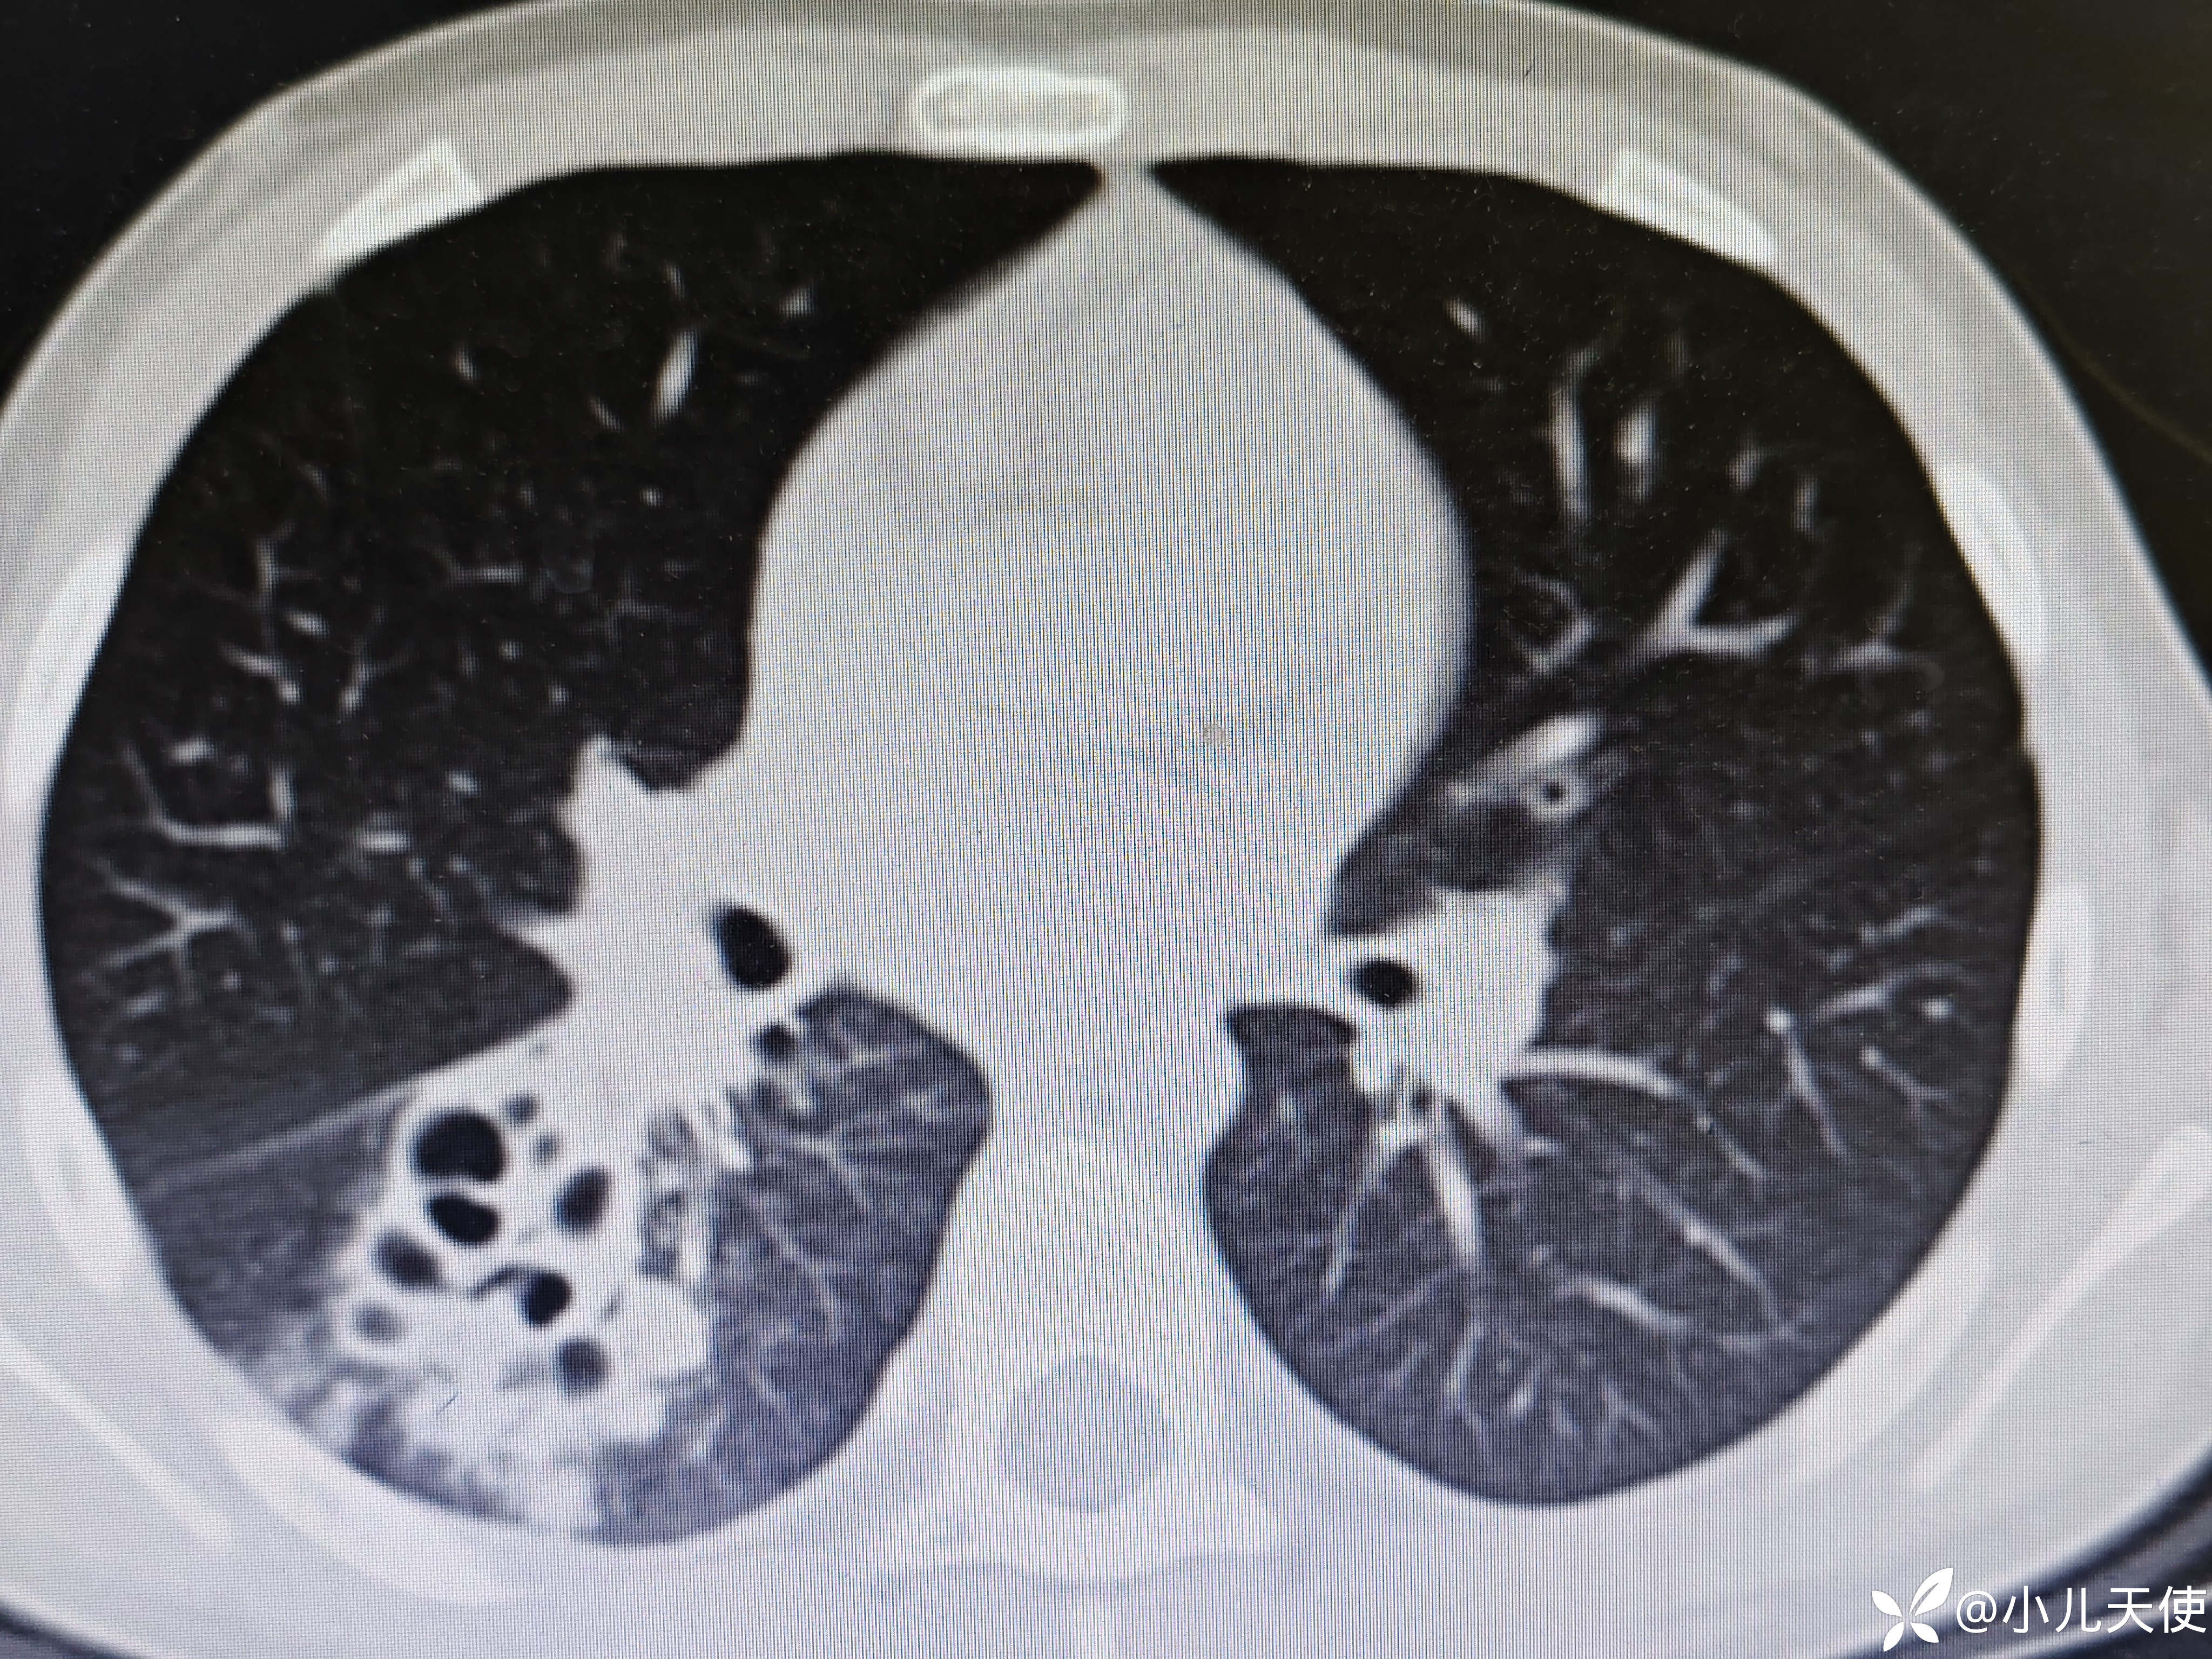

近期6岁女性患儿,发热5天咳嗽4天入院,入院时右肺可闻及明显湿性啰音,支原体衣原体IgM抗体阴性,甲流乙流抗原阴性,腺病毒、结核抗体阴性。血象,CRP、PCT均不高,ESR28,CT见上图。经抗感染(头孢,阿奇霉素)、抗炎(甲强2mg/㎏)等治疗一周,体温第二天即稳定,现肺部啰音已无,咳嗽明显好转,复查胸部CT见下图

CT提示右下肺炎症较前吸收,但提示多发囊性病变,建议进一步行病原学检查。这个还是考虑支原体肺炎肺部损害,还是其它因素所致?(既往未行肺部影像学检查)。望赐教!!